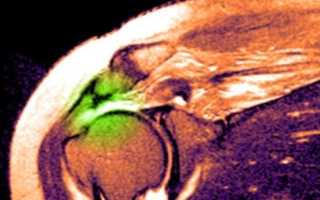

МРТ плечевого сустава. Т2-взвешенная корональная МРТ. Разрыв вращательной манжеты. Цветовая обработка изображения.

image

При МРТ плечевого сустава высоким сигналом на Т2-взвешенных изображениях от поверхности сустава до субакромиальной сумки можно косвенно указать на разрыв вращательной манжеты. Частичные разрывы чаще всего наблюдаются на передней поверхности сухожилия m. supraspinatus, реже — у большой бугристости или сухожилия m. infraspinatus.

МРТ плечевого сустава может показать субакромиальное скопление жидкости, что также является косвенным признаком разрыва вращательной манжеты. Частичный разрыв может быть виден на Т1-взвешенной корональной МРТ, а передний разрыв — на Т2-взвешенной.